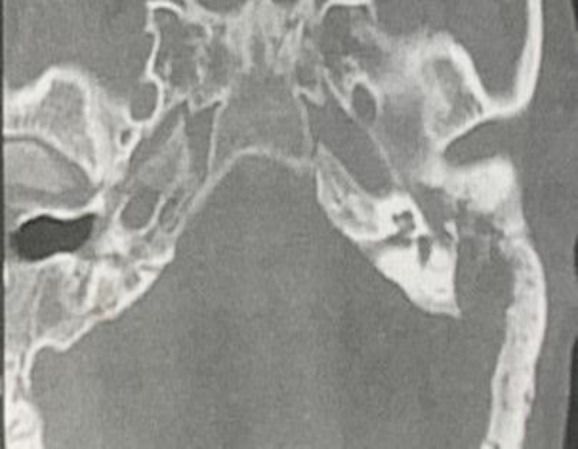

Case report: A 47-year-old patient with a history of both old laryngoscleroma and recent Rhinoscleroma. He presented with symptoms of ear discharge and facial palsy. Examination revealed complete facial nerve palsy and an external auditory canal polyp. A decision was made to perform subtotal petrosectomy with facial nerve decompression and maximum debulking to be sent for histopathology. The result came typical of otoscleroma.